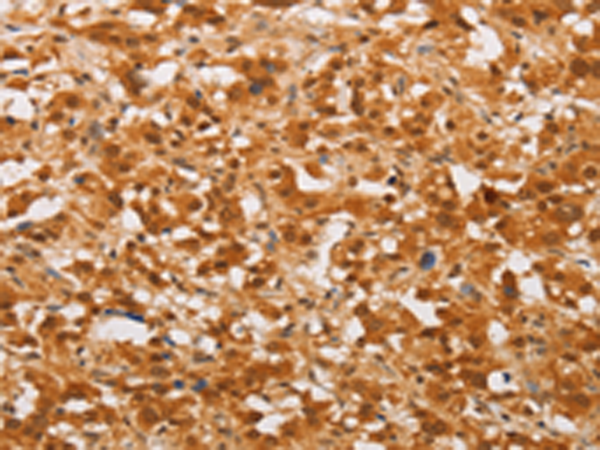

分类: 科研抗体货号: P08022别名: LK4; hCERK; dA59H18.2; dA59H18.3应用: IHC反应种属: Human, Mouse